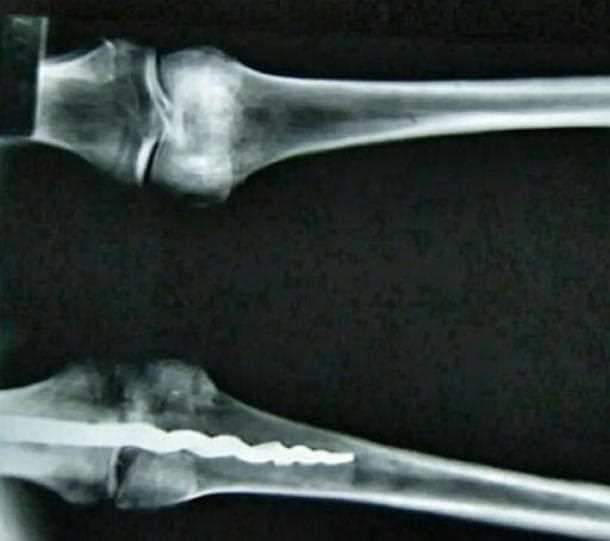

في أواخر التسعينات كان الدكتور "ريتشارد جاكسون" والبروفيسور البروفسور " سي ويلفريد غريغز " وهما بيعملموا اشعة على الجثمان أو المومياء وجدوا جسم غريب في الركبة ظهر في الأشعة !!

طبعًا الجسم مكنش واضح من الأشعة فكان لازم يدخلوا جوه علشان يعرفوا ايه ده فاتعمل زي عملية جراحية بسيطة كدة علشان يدخلوا كاميرا تصور ايه الجسم الغريب اللي في الركبة ده !!

الغريب أن تصميمه لايختلف عن الحديثه وقد تم تثبيته باستخدام مادة "الراتنج العضويه" !!

الأكثر غرابة أن نوع الجراحة ده اتعرف في العالم الحديث سنة 1841 م عن طريق العالم الفرنسي "نيكولا اندري" بس من الواضح أنه كان في مصر القديمة من الأسرة 19 .